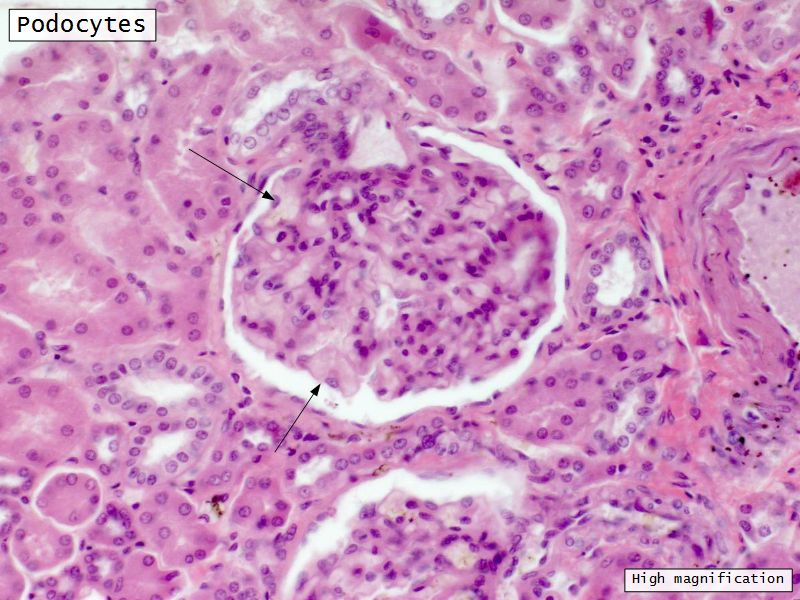

Epithelium layers

Capillary endothelium

Visceral layer of epithelium

Podocytes

Resting on glomerular basement membrane

Capsular space

Parietal layer of epithelium

Simple squamous epithelium

Glomerular filtration barrier

Three layers

Fenestrated epithelium

Exclude blood cells & platelets

Glomerular basement membrane

Main filtration barrier

Thick

Fused epithelial & endothelial BM

Replenished by podocytes due to removal by mesangial cells

Glomerular epithelium

Through filtration slit